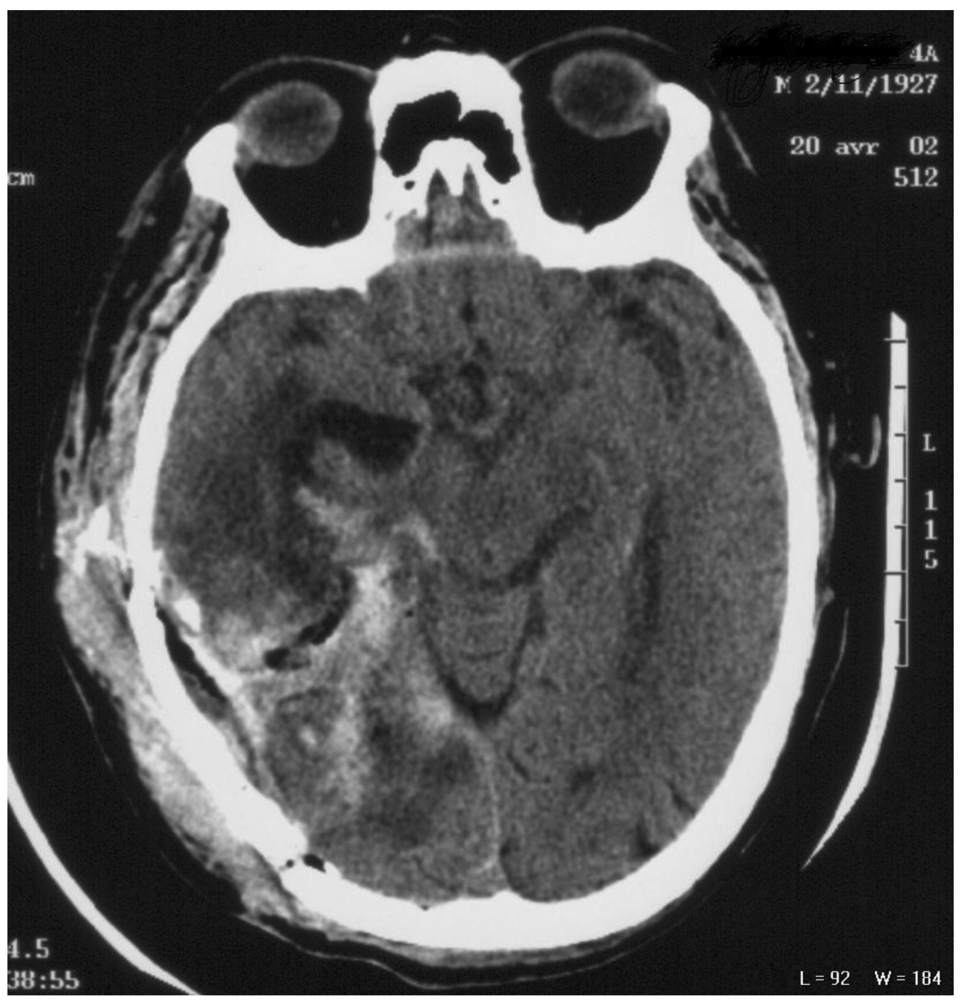

A 74 year-old male with a medical history of pulmonary tuberculosis progressively developed agitation and mental confusion over one month. Neurological examination revealed an intracranial pressure syndrome and a left-sided paresis. A cranial MRI displayed a large heterogeneous enhancing mass in the right temporo-occipital lobe. Surprisingly, the biological parameters revealed hyponatremia and a pancytopenia involving the red blood cells and platelets. A craniotomy was performed with an incomplete tumor resection and a GBM was diagnosed (Figure 1). The post-operative course was excellent with improved patient status; the confusion and intracranial pressure syndrome disappeared and the left-sided paresis was mild.